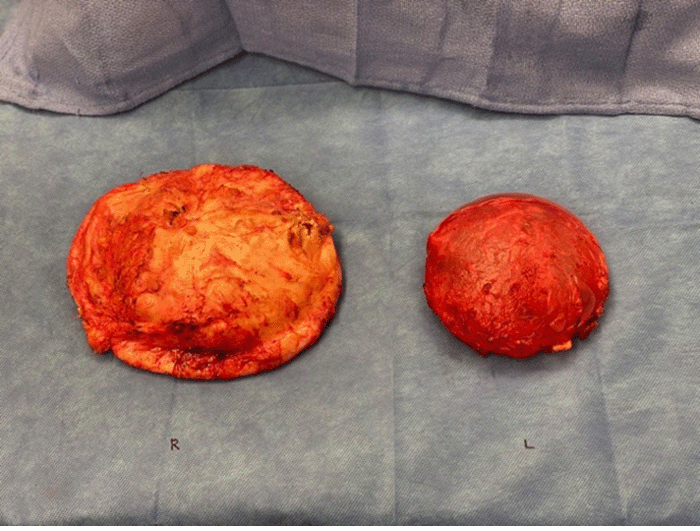

Inframammary incisions were made, and en bloc resection was completed bilaterally (Figure 2A). Both implants were in the subglandular plane. The left implant was smooth and saline-filled; the right implant was textured. The left periprosthetic capsule appeared grossly normal with no intracapsular fluid or evidence of thickening or nodules (Figure 2B). In stark contrast, the right capsule was markedly thickened, with yellowish periprosthetic fluid and white caseous material within the capsule without discrete tumor nodules (Figures 2C and 2D). Both surgical sites were thoroughly irrigated prior to closure, and the patient had an uncomplicated postoperative course.

Figure 2B.

Following en bloc resection of bilateral breast implants and capsules, right capsule was noted to be significantly larger than left capsule